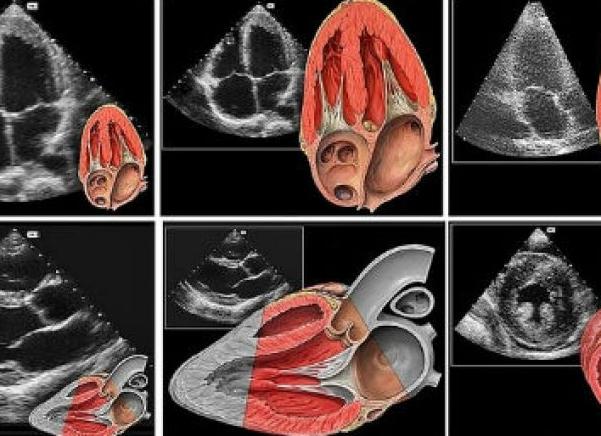

Эхокардиоскопия (ЭхоКС) еще называется эхокардиографией (ЭкоКГ) или попросту ультразвуковое исследование всей сердечной системы. Данный метод достаточно информативный, так как позволяет не только обнаружить увеличенное в объеме сердце, но и также более детально и тщательно исследовать все его составляющие (перегородки, желудочки и сосуды).

Эхокардиоскопия (греч. echo отголосок, эхо + kardia сердце + scopio смотреть): синоним ультразвуковая кардиоскопия, Эхо- КС) — метод исследования и диагностики нарушений морфологии и механической деятельности сердца, основанный на регистрации отраженных от движущихся структур сердца ультразвуковых сигналов.

Для получения изображения сердца по длинной или короткой оси в реальном времени применяется двухмерная эхокардиоскопия, позволяющая оценить размеры полостей сердца, толщину стенок желудочков, состояние клапанного аппарата, подклапанных структур, глобальную и локальную сократимость желудочков, а также наличие тромбоза полостей.

Для графического изображения движения стенок сердца и створок клапанов во времени проводится эхокардиоскопия в М-режиме, что дает возможность оценить размеры сердца и систолическую функцию желудочков.

Использование цветного допплеровского исследования, подразумевающего применение различных вариантов допплера, позволяет оценить параметры центральной гемодинамики.

В настоящее время принято использование всех трех вышеуказанных режимов – т.н. триплексная Эхо-КС.